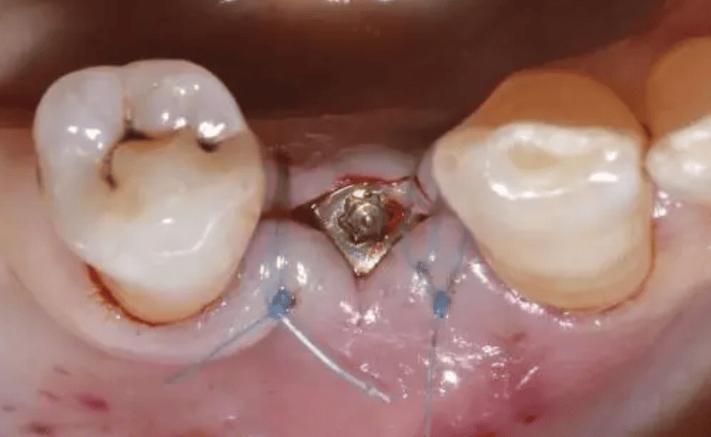

(图片来源网络,侵删)- 可吸收缝线: 这是最常用的种植牙手术缝合材料,这种缝线会在体内逐渐被吸收(通常在1-4周内),不需要专门拆线,医生在手术时使用可吸收线,术后你几乎感觉不到它的存在,它会自行消失。这是目前种植牙手术的主流选择。

- 不可吸收缝线: 少数情况下,医生可能会使用不可吸收的丝线或尼龙线,这种缝线需要按时拆除,否则会长期留在口腔内,可能刺激组织或成为细菌滋生的温床。